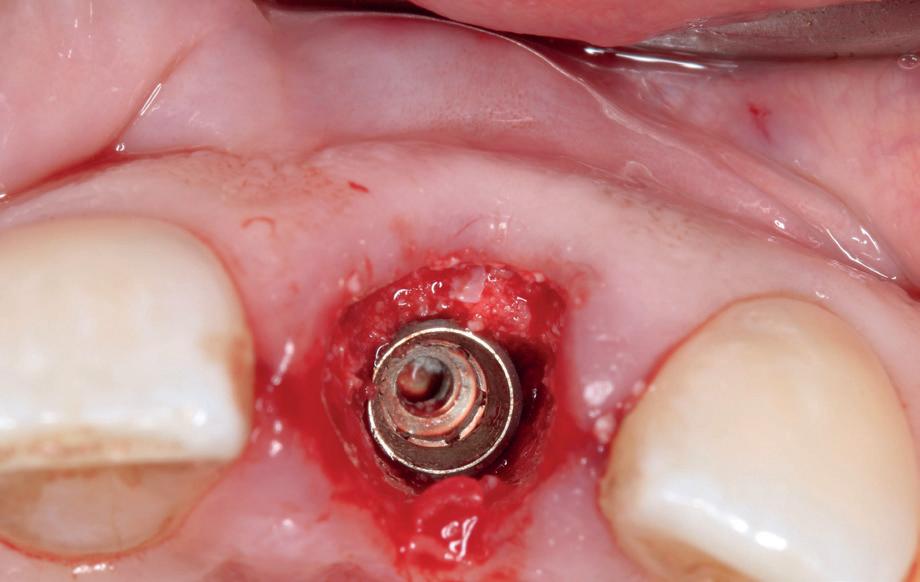

sue-level. Dit naar gelang de locatie in de mond varieert. Voor immediaat implanteren moet er grotere primaire stabiliteit gehaald worden. De implantaten moeten daarvoor langer, agressiever en dikker worden. De vorm van de alveole van het geëxtraheerde element is daarin vaak leidend. We plaatsen implantaten met een afwijkende morfologie, wat niets te maken heeft met het langetermijneffect van de behandeling, maar met hogere initiële stabiliteit. Dus om überhaupt de behandeling te laten slagen, maken we een implantaatkeuze, waar de patiënt niet per se bij gebaat is.

In de zijdelingse delen verwachten we ongeveer 3.5 mm verticaal verlies na extractie van een element. Om dit proces te voorspellen, plaatsen we immediaat geplaatste implantaten om die reden dieper en meer naar linguaal/palatinaal (met bijbehorende risico’s) (afbeelding 2a, 2b).

Daarbij weten we niet waar exact de horizontale en verticale resorptie gaat stoppen. We willen immers kosten wat kost voorkomen dat het ruwe gedeelte van het implantaat onbedekt gaat worden (afbeelding 2c-2f ). Natuurlijk is er 6 mm onder de toekomstige outline van de glazuurcement grens een verwaarloosbaar risico, maar daar had je delayed geplaatste implantaat niet gestaan. Die had slechts 3

mm onder de toekomstige CEJ gestaan. Kortom, we nemen risico’s in de locatie van het implantaat met kans op ruw oppervlakte onbedekt, die niet in het belang van de patiënt zijn.